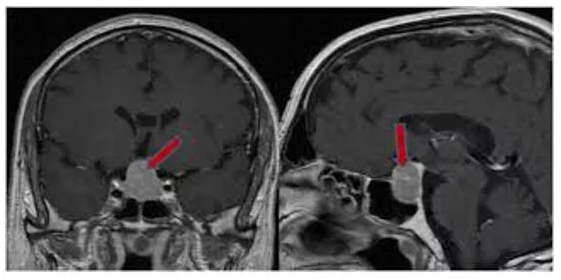

Hipofiz adenomu bulguları saptanan hastalarda öncelikle kan hormon testleri ve görme muayenesi yapılır. Kesin tanı için hipofiz Manyetik Rezonans Görüntüleme tetkiki gereklidir. Cushing Hastalığında çok nadiren beyin anjiyografisi yapılarak hipofiz bezinin komşuluğundan kan örneği alınması gerekebilir.